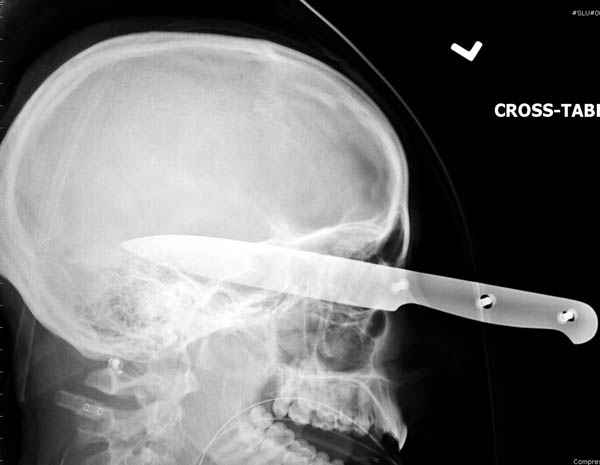

В своих выступлениях я рассказывал, что наши центры в мирное время по пенетрирующим травмам не уступает Ираку или Афганстану, и вот недавно к нам поступила больная 22 лет, травма "ножом в глаз" от бывшей подруги нынешнего "бой френда".

При поступлении в сознании, жаловалась на неприятные ощущения в глазнице.

По протоколу сделаны все необходимые исследования: рентген, ангиограмма с 3Д реконструкцией, где обнаружили что все жизненно важные сосуды не задеты, даже некоторые "сидят" изгибаясь на ноже.